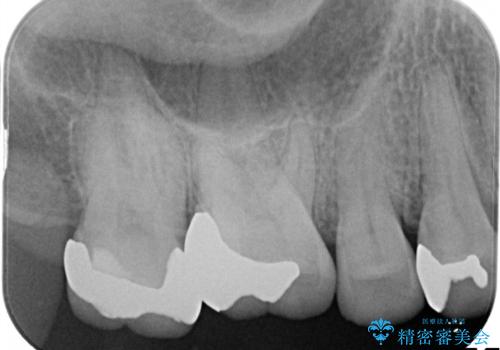

銀歯が外れてしまった ゴールドインレーによる補綴治療

- 銀歯が外れて、中が虫歯になっているところがありました。

虫歯を取り除き、ゴールドインレーを装着する治療計画としました。

ゴールドは目立つという欠点がありますが、適合が良く、割れることもないため、長期的に安定した治療法となります。